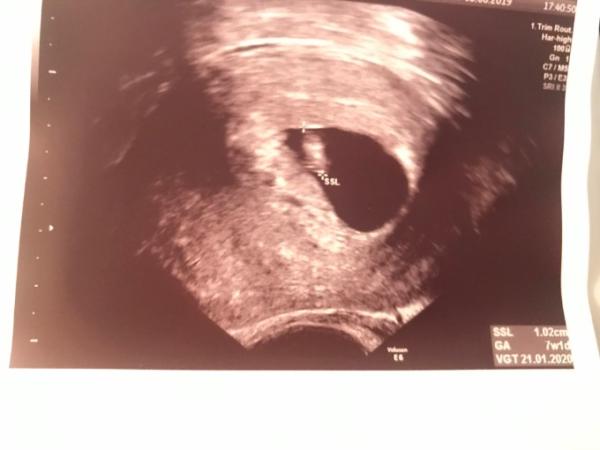

Hallo zusammen, traue mich gar nicht so recht, hier meine Freude zu teilen, weil manche aus diesem Forum zeitgleich ihr Kleines wieder loslassen müssen Möchte dennoch mit Euch teilen, dass ich heute bei der ersten „richtigen“ Vorsorgeuntersuchung war und meinen Mutterpass erhalten habe Bin rechnerisch bei 7+5, sie sagte könnte auch 7+1 sein, errechneter Termin erstmal 18.01.2020 aber kann sich natürlich noch etwas verschieben. Mein Freund war zum ersten Mal auch dabei, wir haben uns an den Händen gehalten als der Herzschlag zu sehen war wir hatten emotional und beziehungstechnisch jetzt 2 schlimme Tage hinter uns, da ich doch um einiges früher schwanger geworden bin als geplant (jobmäßig/finanziell). Aber ab heute geht es wieder aufwärts und ich kann mich nun etwas entspannen und seit 1-2 Stunden auch mal wieder lachen...ich DANKBAR bis hierher und wünsche allen die noch mit im Bus sind dass wir alle auch dabei bleiben

Bild zu Mutterpass und Brimborium - Forum für Januar - Mamis